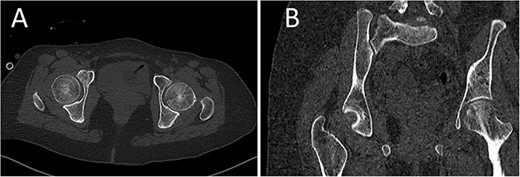

A medically free 42-year female presented to our institute as a life-saving case from a different hospital as she was a victim of unrestrained road traffic accident 2 days prior to presentation. Upon assessment in the emergency department (ER), she was conscious and oriented, and was found to have bilateral lung contusion, and multiple fractures of ribs. She also had a left sided vertical femoral head fracture dislocation comprising around 40% of the femoral head (Fig. 1). Closed reduction under conscious sedation was done in the ER, which was successful based on post-reduction imaging studies (Fig. 2). Her chest injuries were treated with chest tube and observation for 10 days. During that time, discussion was made with the patient regarding her situation and conservative management was chosen by way of bed rest and continuation of skeletal traction for 4 weeks with serial radiographs in the hospital on a weekly basis after clearance of her chest injuries. Skeletal traction was discontinued and she was advised to continue bed to wheelchair mobilization for an additional 2 weeks. After 6-weeks from the injury, a Computed Tomography (CT) was done to the patient and revealed signs of fracture healing (Fig. 3). At 3-years after the injury, she was found to have full painless range of motion of the affected hip and has resumed her activity of daily living without any complaints and the images showed a symmetrical joint space of the hips (Fig. 4).

AP radiographs (A) and frog leg lateral (B) radiographs at 3-year follow-up showing a concentrically reduced hip.